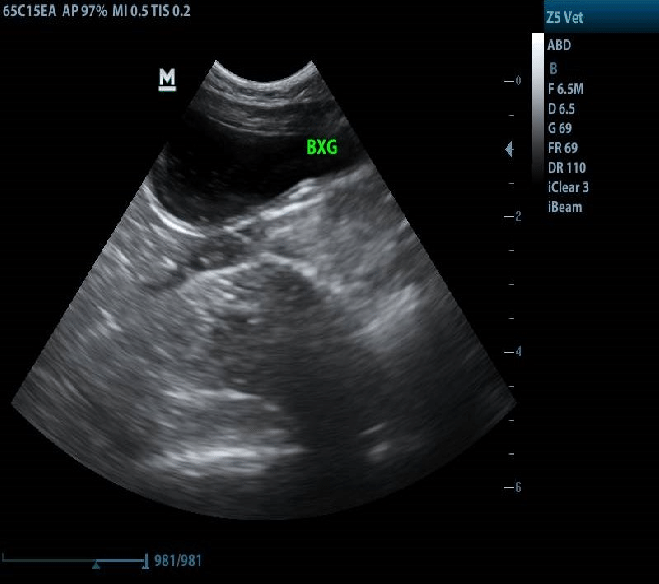

🩺 Diagnóstico e Tratamento

O diagnóstico envolve exames como urina, ultrassom, tomografia e cistoscopia (procedimento que visualiza a bexiga internamente).